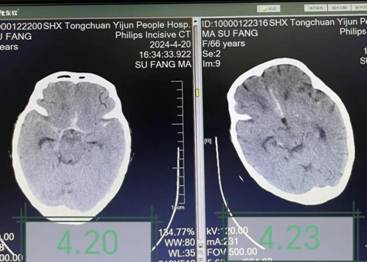

治疗前后颅脑CT对比,颅脑水肿及出血减轻

患者入院前2天蛛网膜下腔出血于西安某三甲医院神经外科ICU住院治疗,期间突然陷入深昏迷,且患者高龄、一般状况差、生命体征不稳定,主管医生告知家属患者病情极其危重,无手术机会,继续治疗意义不大。面对这一沉重打击,患者家属万念俱灰,放弃在西安继续治疗,转回宜君县人民医院拟行姑息治疗。了解病情后,医疗团队详细查阅患者病历资料,认真细致查体,患者生命体征不平稳,深昏迷状,疼痛刺激无反应,颈项强直。经讨论分析,患者突发昏迷的原因可能为再出血及脑血管痉挛,同时存在代谢性酸中毒、肺炎、电解质紊乱等影响脑功能,充分评估后,团队建议进行腰椎穿刺及脑脊液置换术。经与家属详细沟通,征得同意后连夜安排手术。手术由神经内科主治医师李妮妮操作,术中可见血性脑脊液流出,经多次脑脊液置换,脑脊液血色逐渐变淡,约半小时顺利结束手术。术后继续给予止血、营养神经、抗感染、纠酸、呼吸支持等综合治疗。在医护人员的精心照料下,次日查房患者意识转清,头痛症状明显缓解,能够与家属及医护人员正常交流,四肢活动也有明显恢复,复查颅脑CT显示出血及水肿情况较前减轻。经过3天巩固治疗,患者病情基本稳定。面对患者奇迹般的恢复,家属对治疗团队的敬业精神和高超医术表示惊叹及深深的感谢。